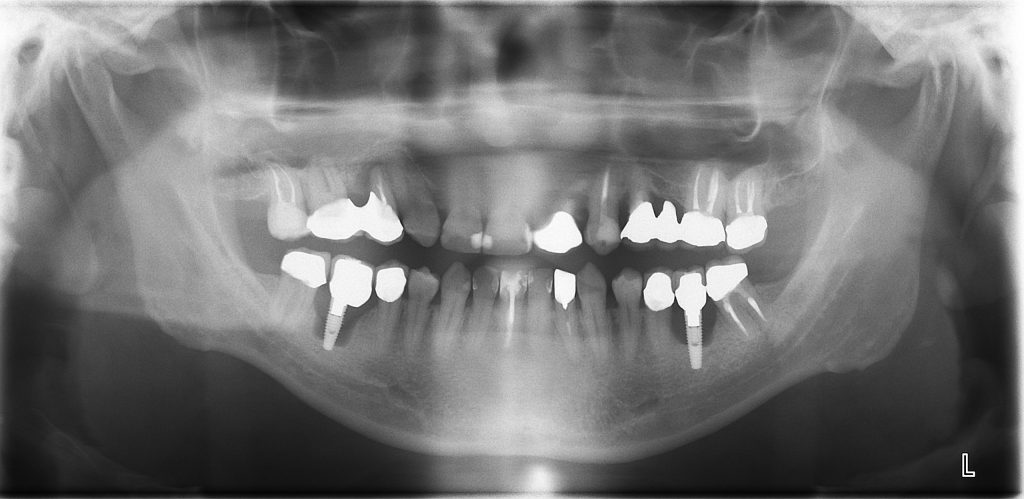

症例紹介